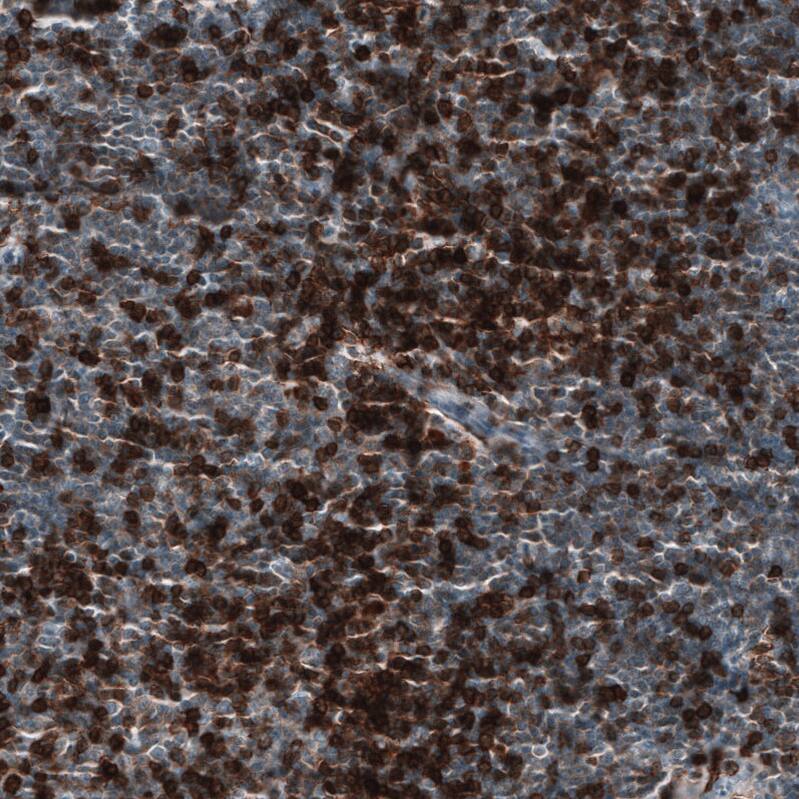

Immunohistochemistry-Paraffin: CD5 Antibody [NBP3-44362]

Staining of human chronic lymphocytic leukemia shows strong membranous positivity in tumor cells.